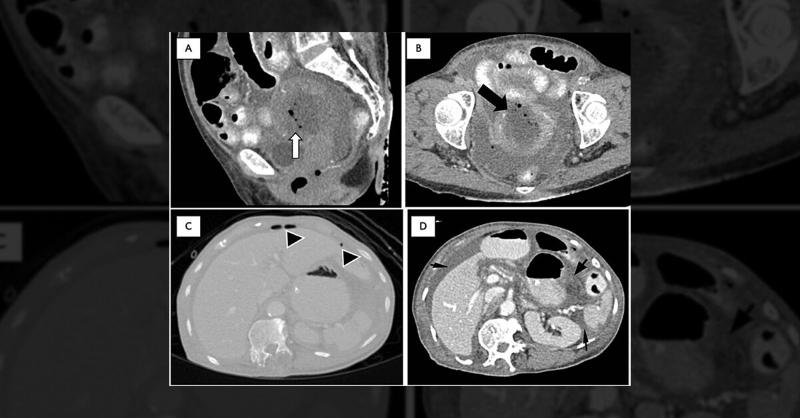

A 75-year-old postmenopausal woman presented to the emergency department with sudden abdominal pain, preceded by a two-day fever and vomiting. The dull, aching pain worsened with movement. She had no altered bowel habits, maintained flatus passage, and had no family history of malignancy. Medically treated for asthma, hypertension, and hyperlipidem